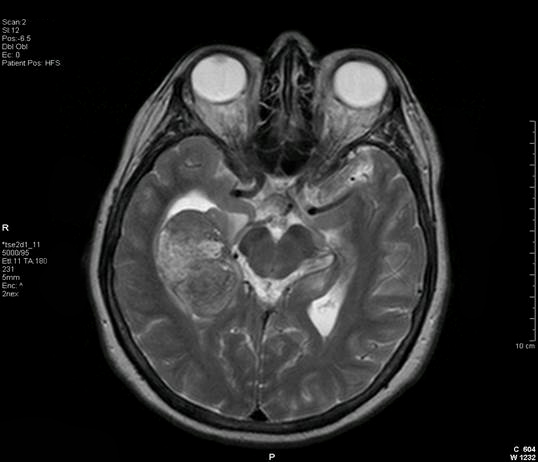

The MR images below show a brain tumor in the right temporal lobe that was found after the patient had a seizure, which is how many brain tumors are first discovered. The lower image demonstrates the stereotactic surgical approach to the tumor (Images courtesy of Dr. McMurtrey)